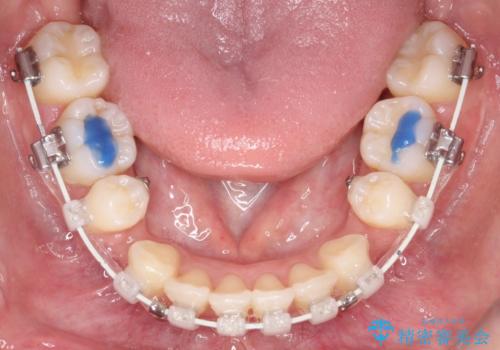

2. 【審美ワイヤー】口元を下げたいの治療中